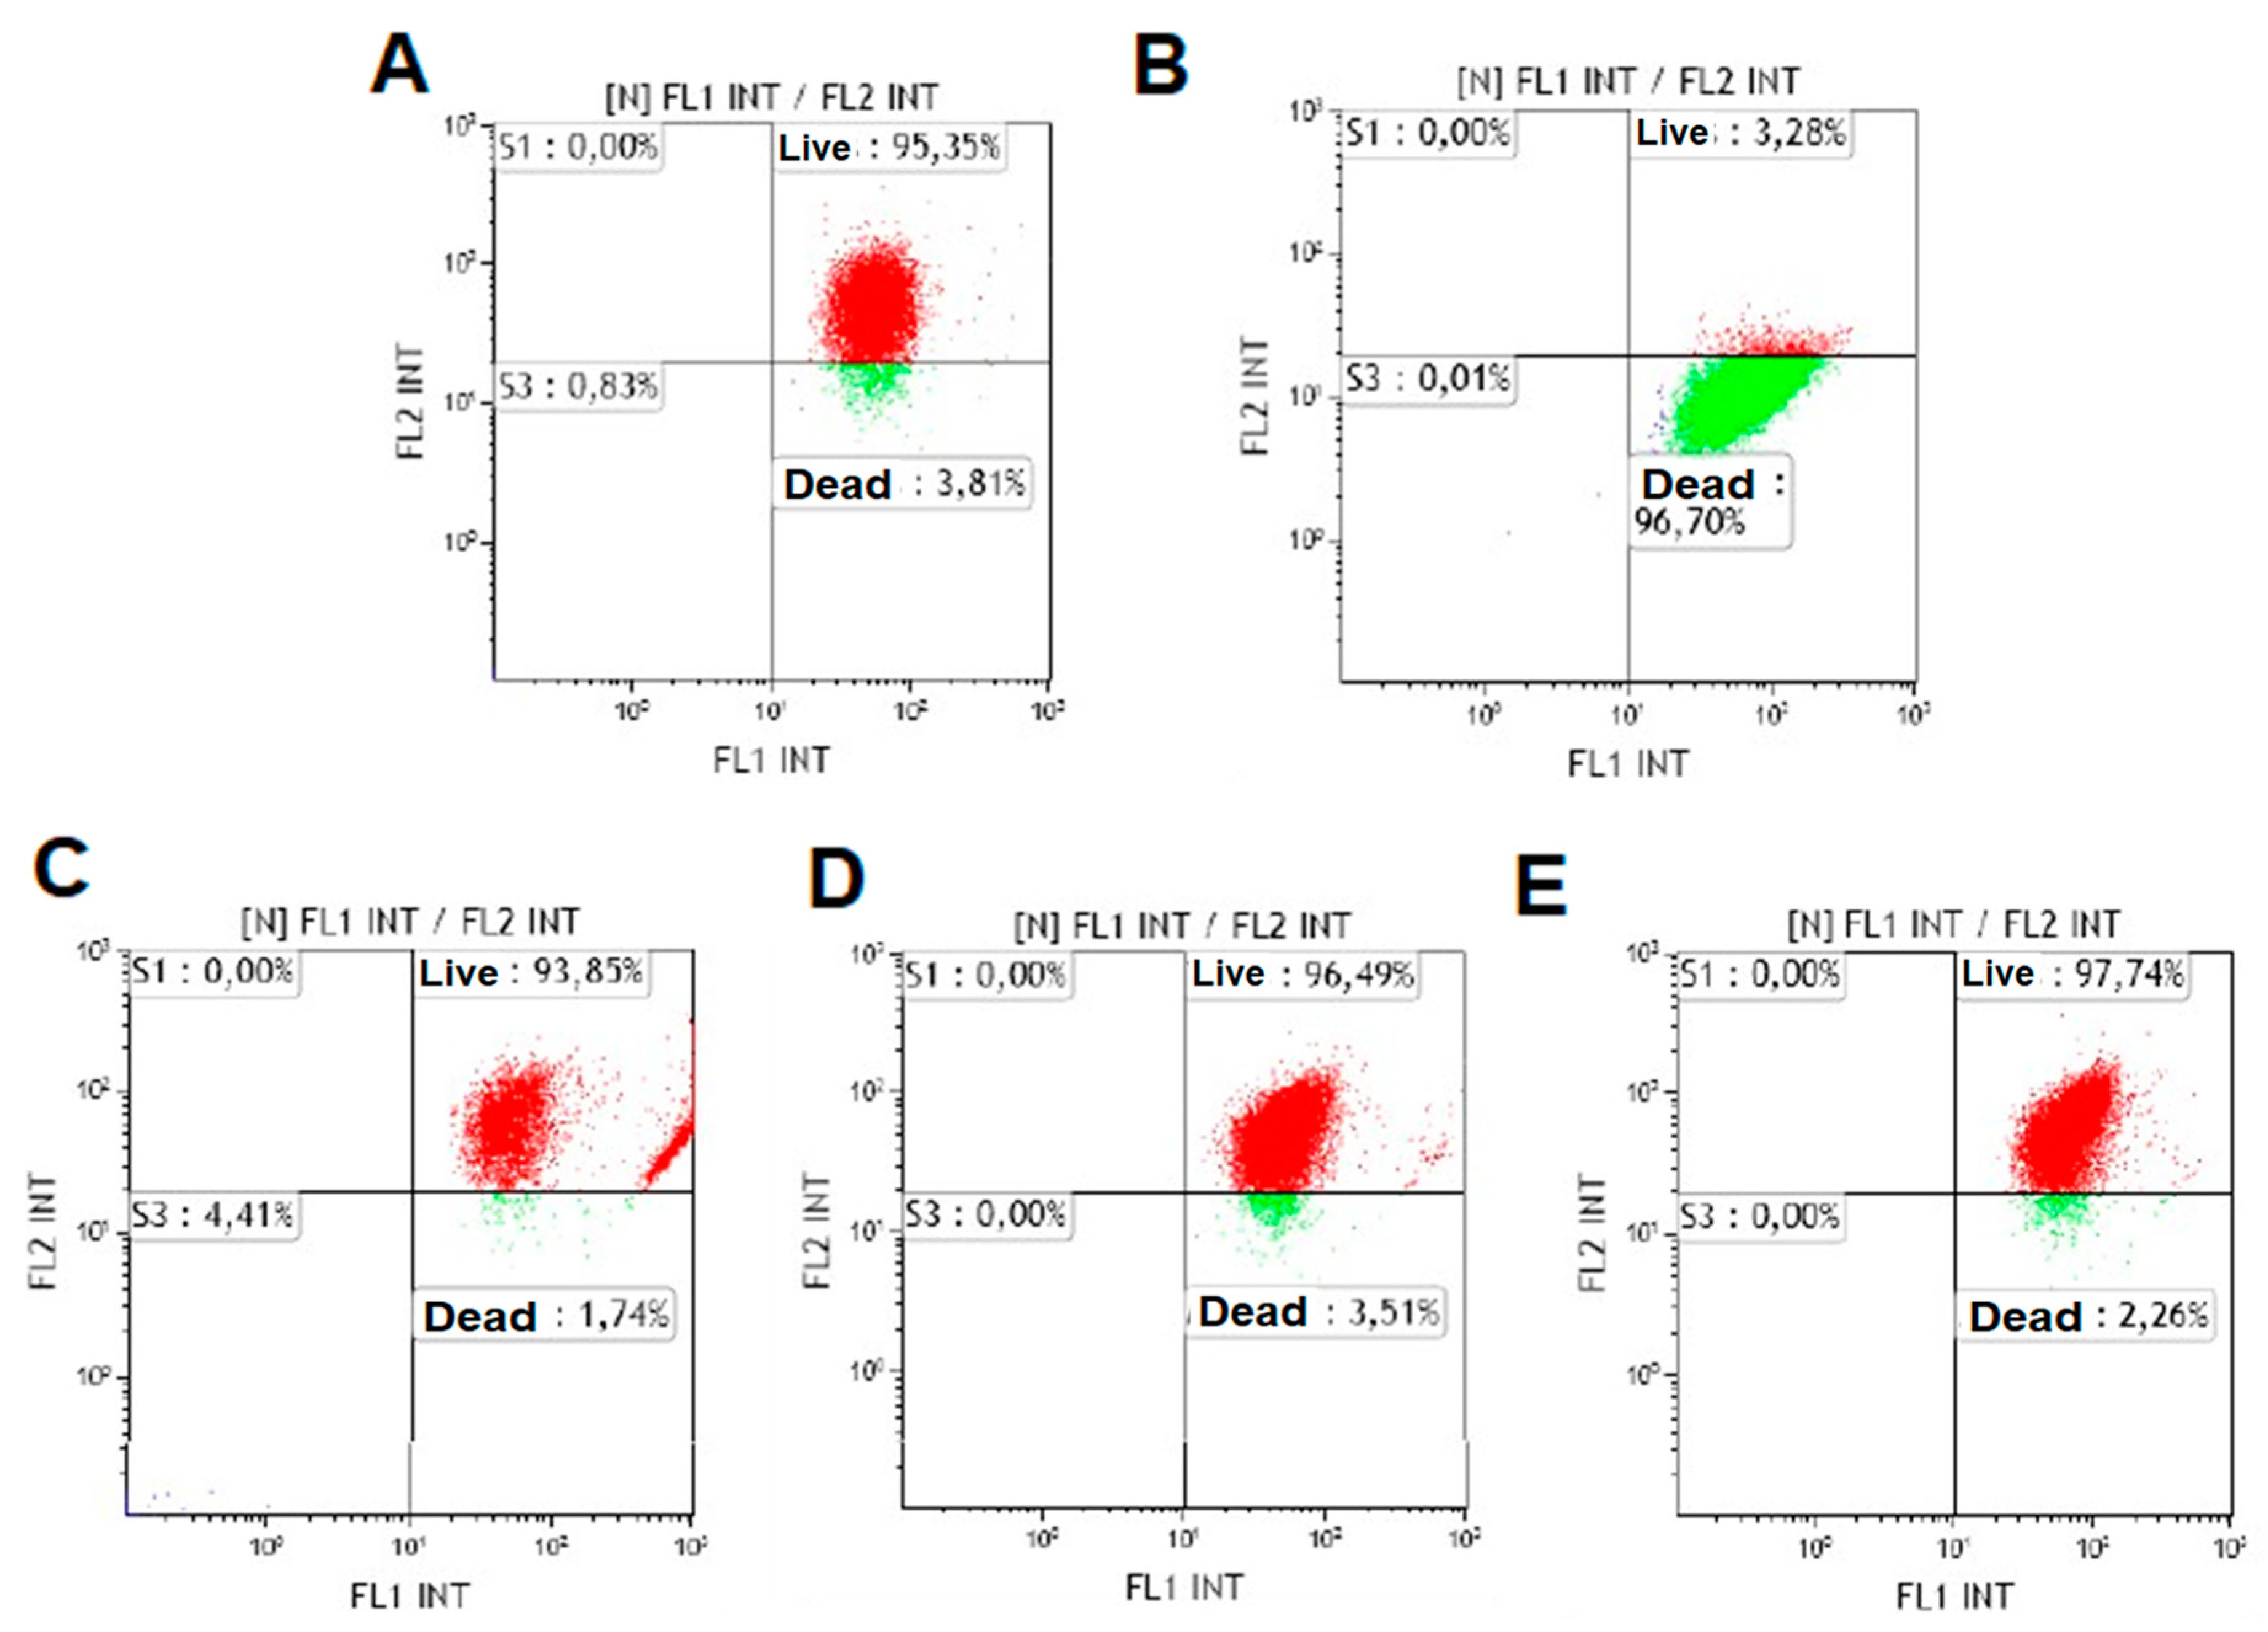

2.3. Cell Viability Study

3.2. Cell Viability Study